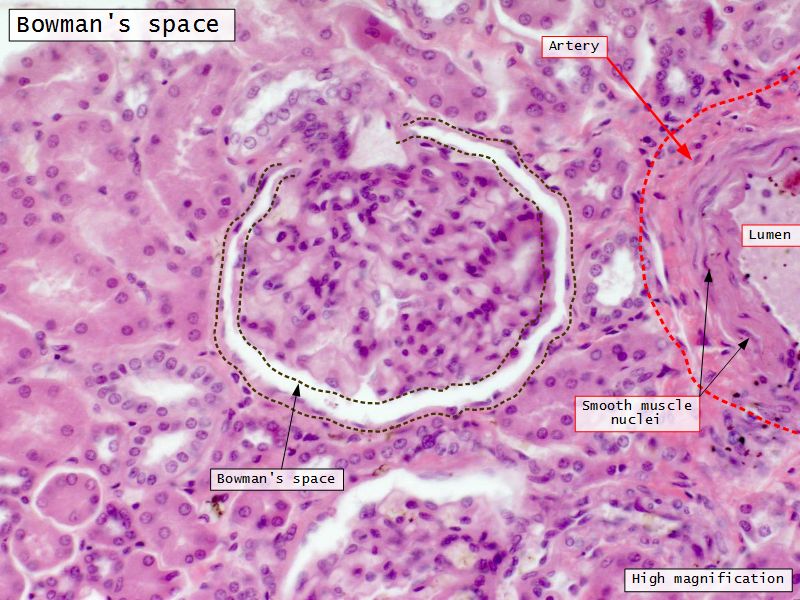

Renal corpuscle

- Tuft of capillaries

- grow into

- Blind end of nephron

- Several layers of epithelium

- Two sides

- Vascular pole

- Tubular pole

Epithelium layers

- Capillary endothelium

- Visceral layer of epithelium

- Podocytes

- Resting on glomerular basement membrane

- Capsular space

- Parietal layer of epithelium

- Simple squamous epithelium